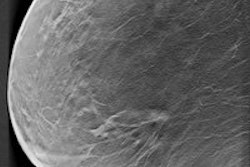

The aim was to investigate whether NBCSP fulfills its intentions and purpose, in this case a target of 30% mortality reduction. In Norway, all women ages 50 to 69 are invited for mammography screening every two years. The program was launched as a pilot project in four counties between 1995 and 1997 and went national in 2004. The stepwise process meant the council could compare women invited for screening with those not invited. A special registry provides information on the date of exposure and attendance, as well as the results of mammograms.